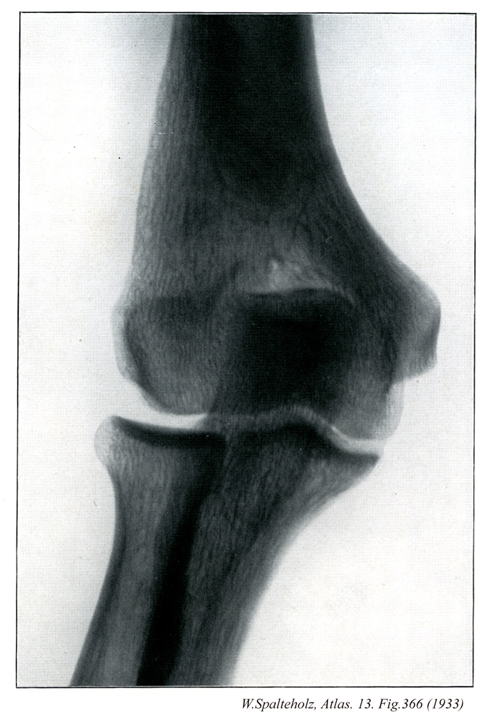

- 366_00【Elbow joint肘関節 Articulatio cubiti】 Joint formed by the humerus, radius, and ulna.

→(肘関節は上腕骨と橈骨、尺骨の3骨の間に生じた複関節で、肘の屈伸を行う。したがって分類状は1軸性の蝶番関節とみることができる。上腕骨滑車と尺骨の滑車切痕との間の腕尺関節、上腕骨小頭と橈骨頭との間の腕橈切痕との間の上頭尺関節が共通の関節包におおわれる。しかし後者は機能的には下橈尺関節とともに前腕の回旋に関係するので、前2者とは別に記載するのが通例である。上腕骨の内側および外側上顆は関節包におおわれない。関節包の内側と外側はそれぞれ内側側副靱帯および外側側副靱帯によって補強される。橈骨輪状靱帯は、関節包の内面が肥厚した幅約1cmの靱帯で、尺骨の橈骨切痕の前縁からおこり、橈骨の関節環状面を輪状にとりまいたのち、再び尺骨の橈骨切痕の後縁につく。この靱帯の関節腔に面した部分は軟骨性となり、尺骨の橈骨切痕とともに上橈尺関節における関節窩を形成する。肘関節における屈伸運動の役割を演ずるのは腕尺関節である。しかし上腕骨滑車の内側部の直径が外側部のそれよりやや大きいため、肘を伸ばすと、その時の尺骨の長軸は、上腕骨長軸よりも外方へ約10~20°の傾きを示す。この角をcarrying angleという。しかし肘を曲げたときは、両骨の長軸は重なり合う。)